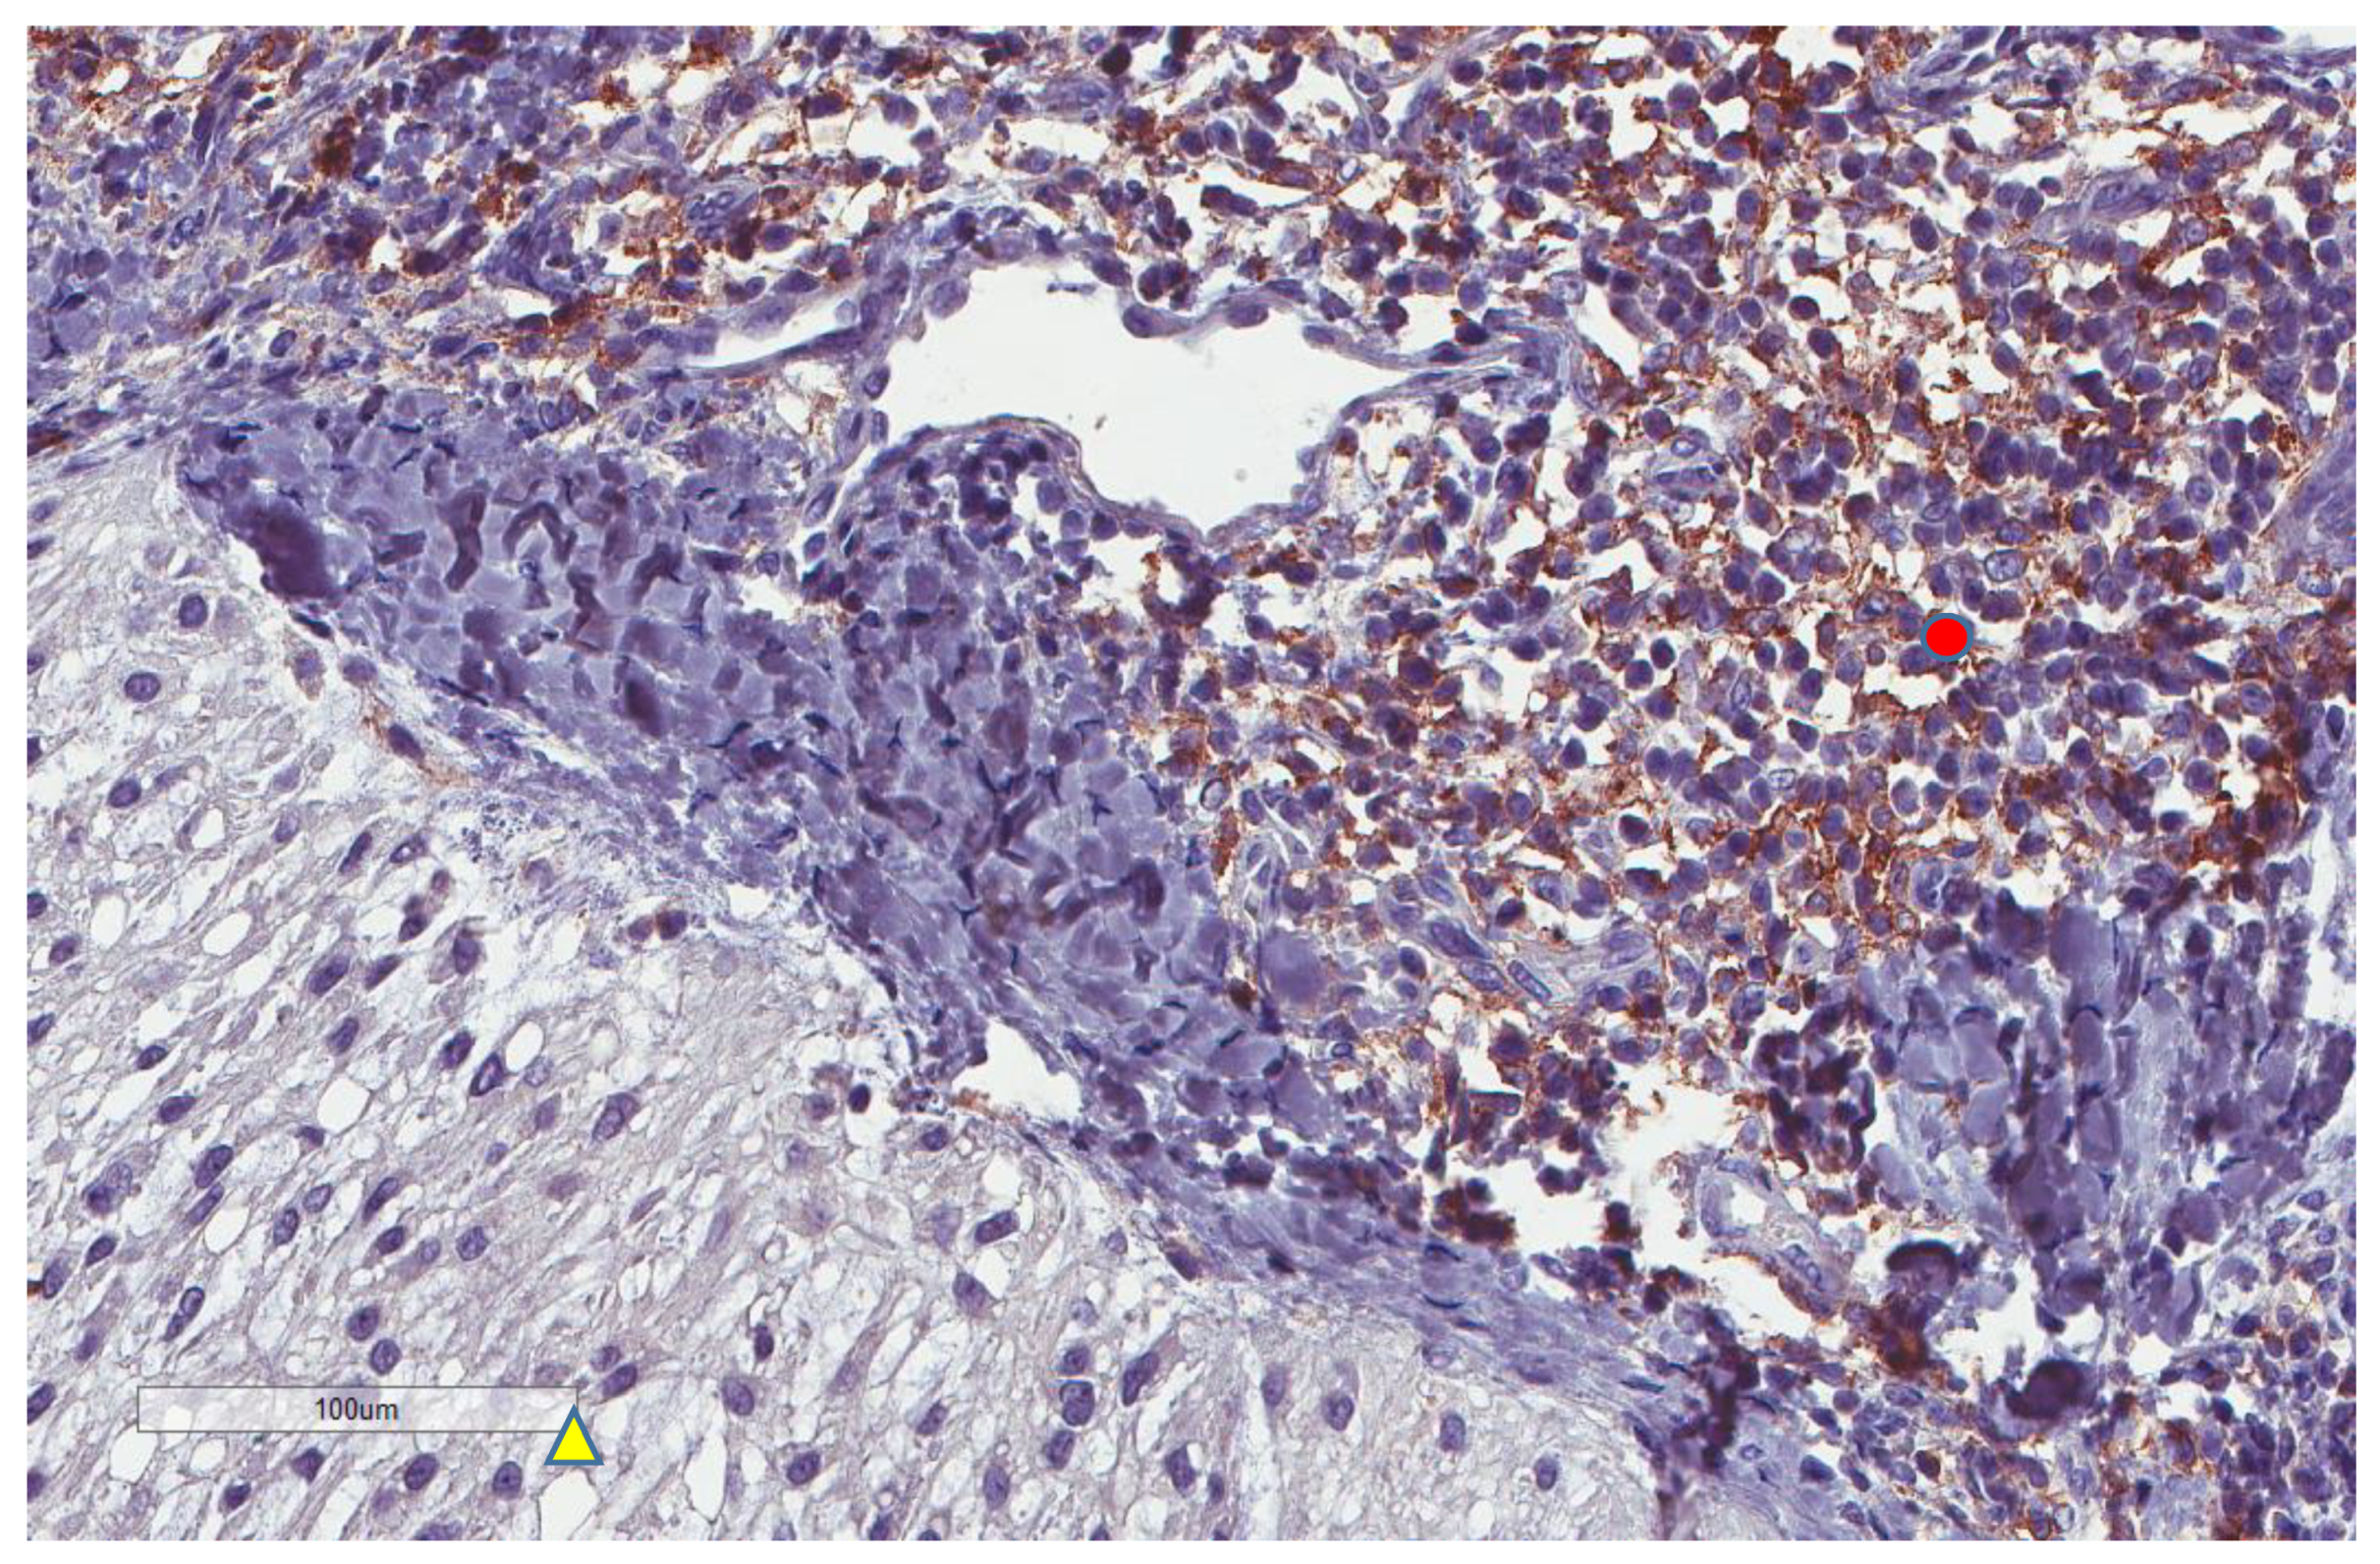

| PD-L1 inflammatory cells (n = 81) | |

| No (score 0) | 60, 74% |

| Yes (score 1–3) | 21, 26% |

| CD34 vascular density (n = 74) | |

| Range | 1–22 |

| Median (High and Low, n,%) | 3.5 (37, 50% and 37, 50%) |

| Mean ± SD | 5.8 ± 5.7 |

| MECA-79 vessels (n = 59) | |

| High | 5, 8.5% |

| Low | 54, 91.5% |